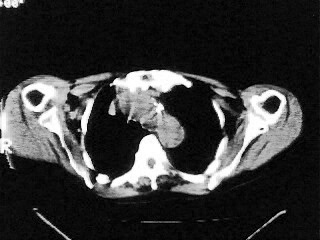

女,79,咳 嗽月余,无其它不适

后纵隔内左心房至肝左叶后方椎体中线偏左巨大软组织包块,其壁均匀比较薄,其内可见宽气液平。

考虑食管裂孔疝。建议钡餐检查